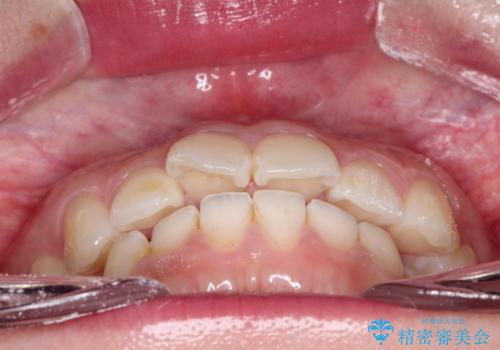

【インビザライン】前歯が出ているのを治したい

- 前歯が出ていることを主訴に来院されました。

前歯の突出感が改善され、満足していただきました。